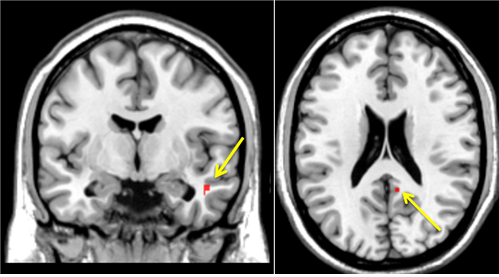

서울의대 윤창호 교수(분당서울대병원 신경과)팀이 수면무호흡증이 알츠하이머병 발병 위험을 높인다는 연구를 발표했다. 이 논문은 '수면무호흡증'에 의한 아밀로이드 침착을 사람 뇌에서 확인한 세계 최초의 연구결과다.

또 "알츠하이머병은 보통 65세 이후에 시작하지만, 원인이 되는 아밀로이드 침착은 이보다 앞선 40-50대에 시작되기 때문에 이 연령대의 대상자를 통해 수면무호흡증에 의한 아밀로이드 침착이 이미 시작됐음을 확인했다"며 "알츠하이머병이 생긴 이후에는 쌓인 아밀로이드를 제거해도 질병 진행과 증상의 경감에는 아무런 효과가 없어 아밀로이드 침착을 막기 위해 미리미리 수면무호흡증을 치료할 필요가 있다"고 강조했다.